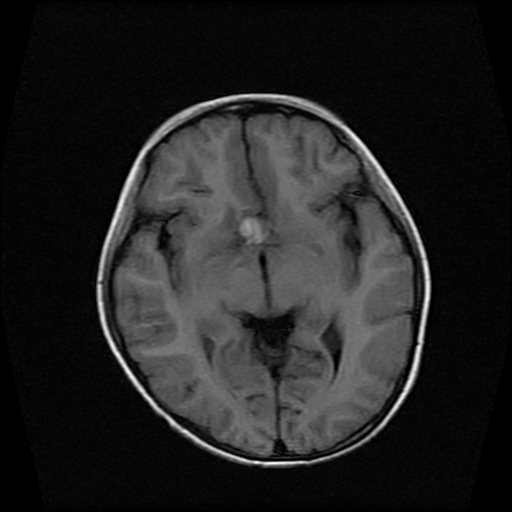

男性,12岁。反复头痛呕吐半月。脑积液无异常。病变部位ct值32hu,dwi无异常。

鞍内囊性占位性病变,t1wi、t2wi,均为高信号影。ct平扫为等密度。发病年龄较小。故首先考虑颅咽管瘤,可以做ct增强扫描

鞍内囊性占位性病变,t1wi、t2wi,均为高信号影。ct平扫为等密度。发病年龄较小。故首先考虑颅咽管瘤。